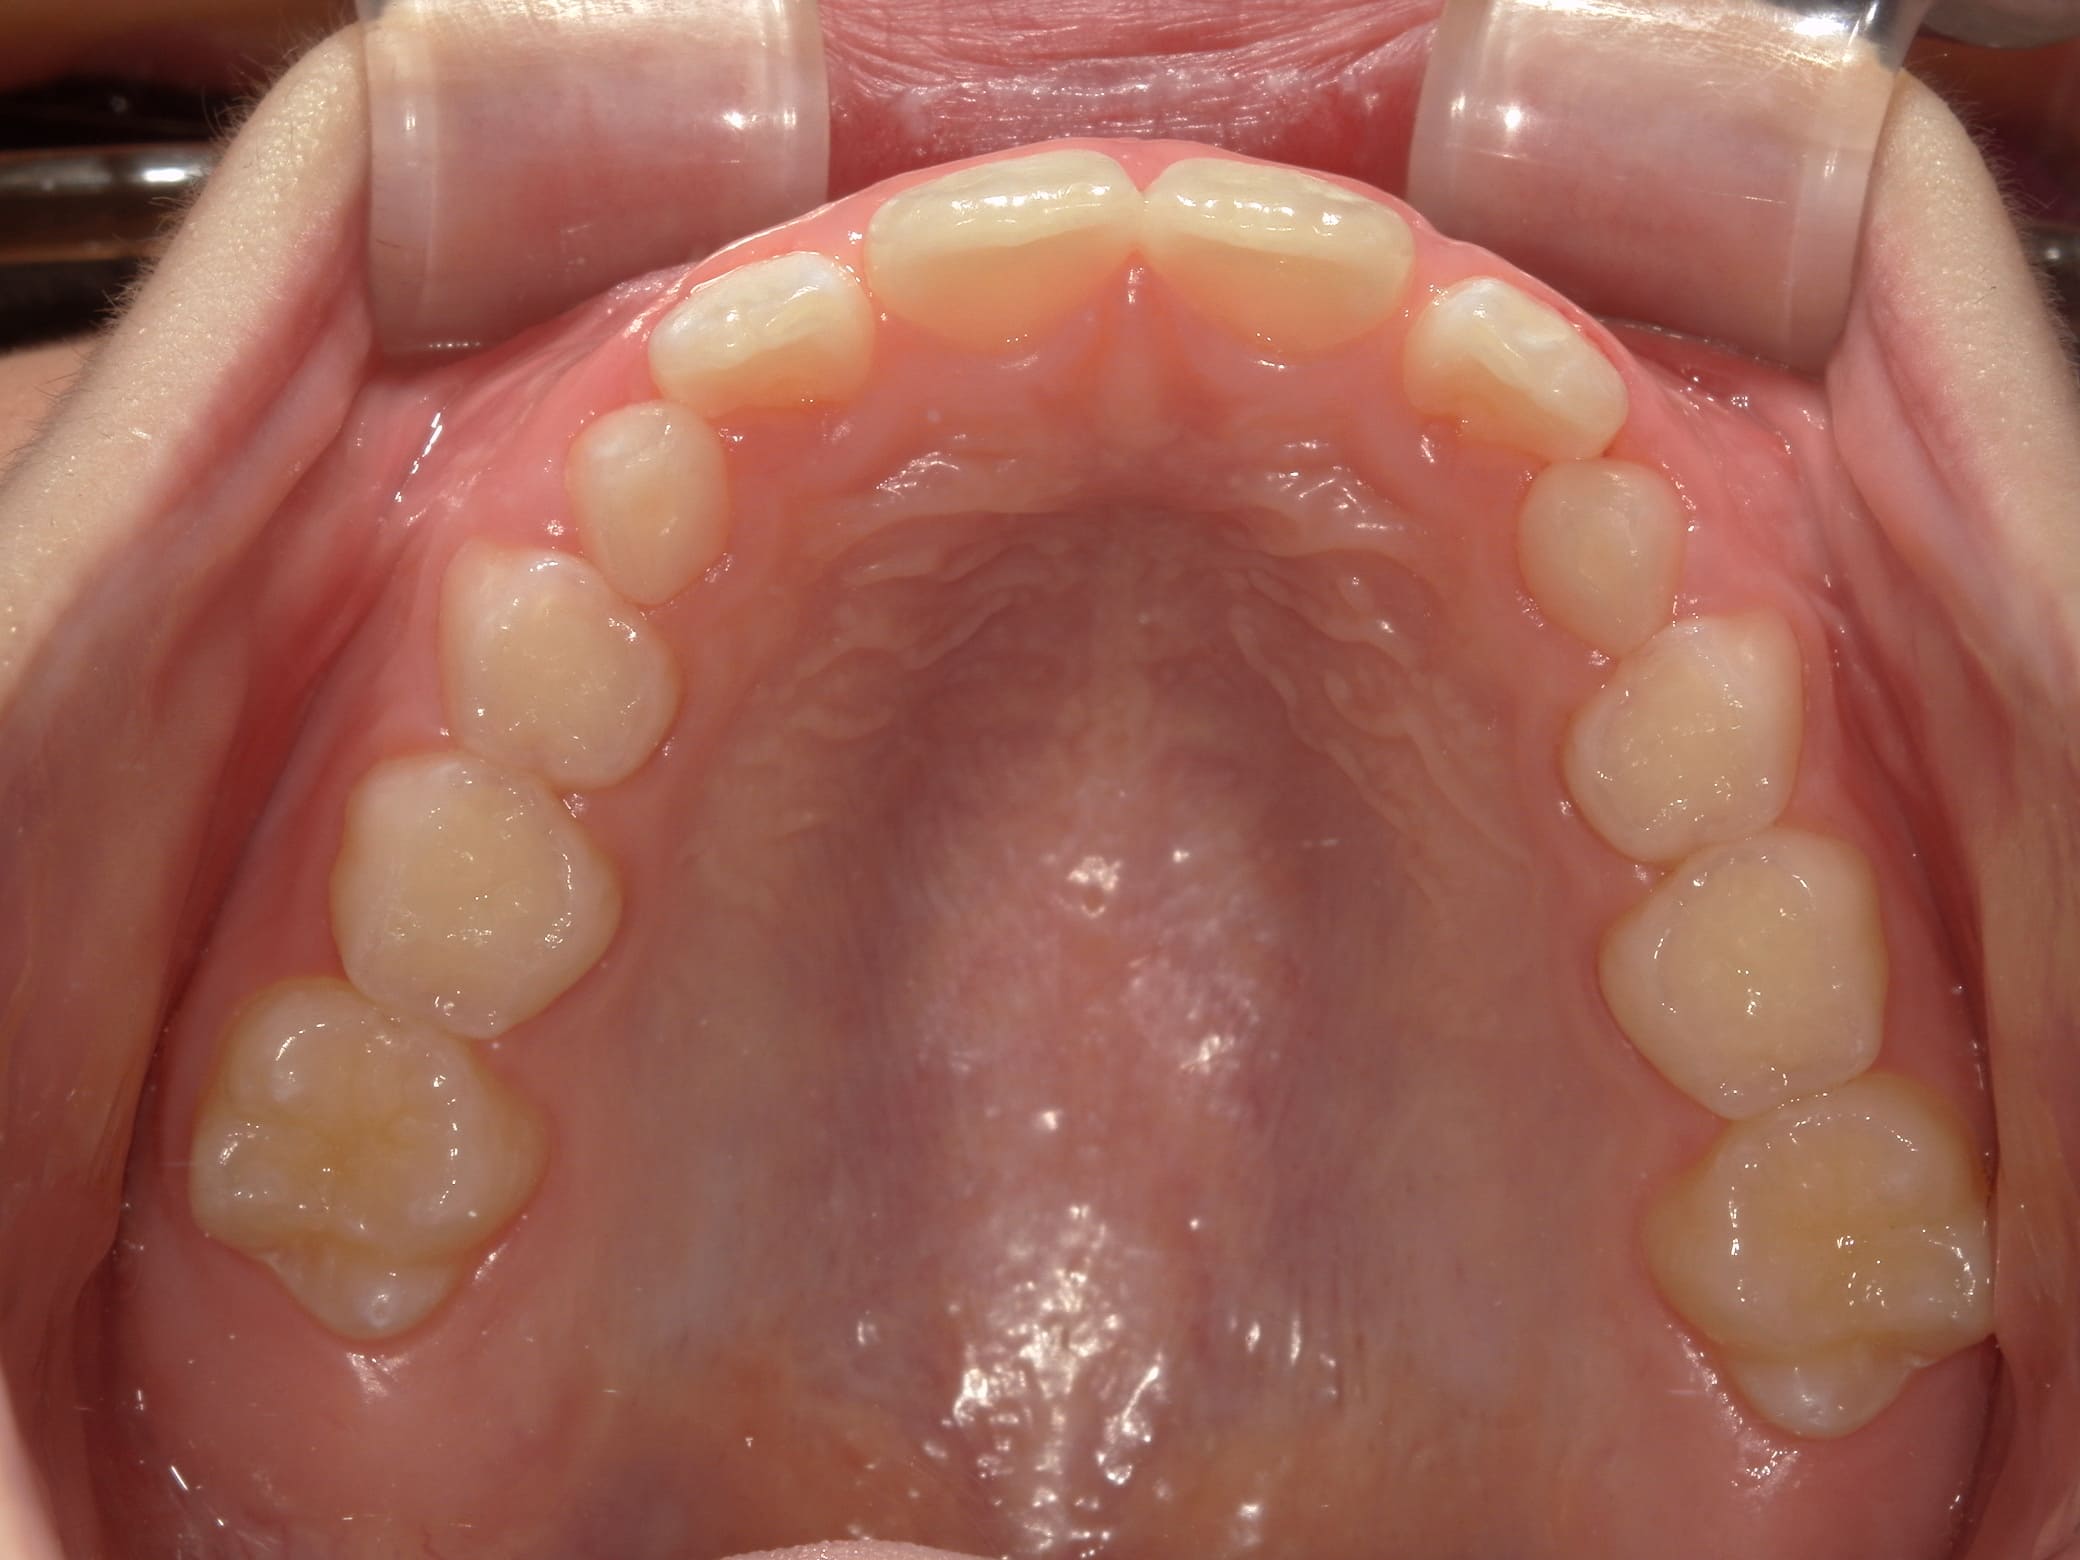

| 年齢・性別 | 7歳1ヶ月の男児 |

|---|---|

| 主訴 | 歯の生えるスペース不足が懸念され、歯列の乱れ(叢生)を整えるために来院された患者様です。 |

| 治療期間・回数 | 1年3ヶ月・11回 |

| 費用 | 420,000円(税別) |